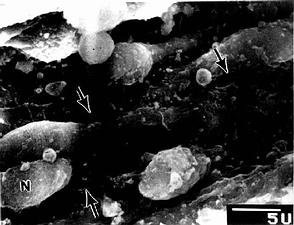

大鼠脾血窦扫描电镜像

图9-22 大鼠脾血窦扫描电镜像

N内皮细胞核,↑内皮质间隙

脾血窦(splenic sinus):是一种静脉性血窦,宽约12~40μm,形态不规则,相互连接成网。窦壁由一层长杆状的内皮细胞平行排列而构成。内皮细胞之间常见许多0.2~0.5μm宽的间隙,脾索内的血细胞可经此穿越进入血窦(图9-21,9-22)。内皮外有不完整的基膜及环行网状纤维围绕,故血窦壁如同一种多孔隙的栏栅状结构。在血窦的横切面上,可见杆状内皮细胞沿血窦壁呈点状排列,较粗大的内皮细胞断面中可见有细胞核,并突入管腔(图9-19)。血窦外侧有较多的巨噬细胞,其突起可通过内皮间隙伸向窦腔。